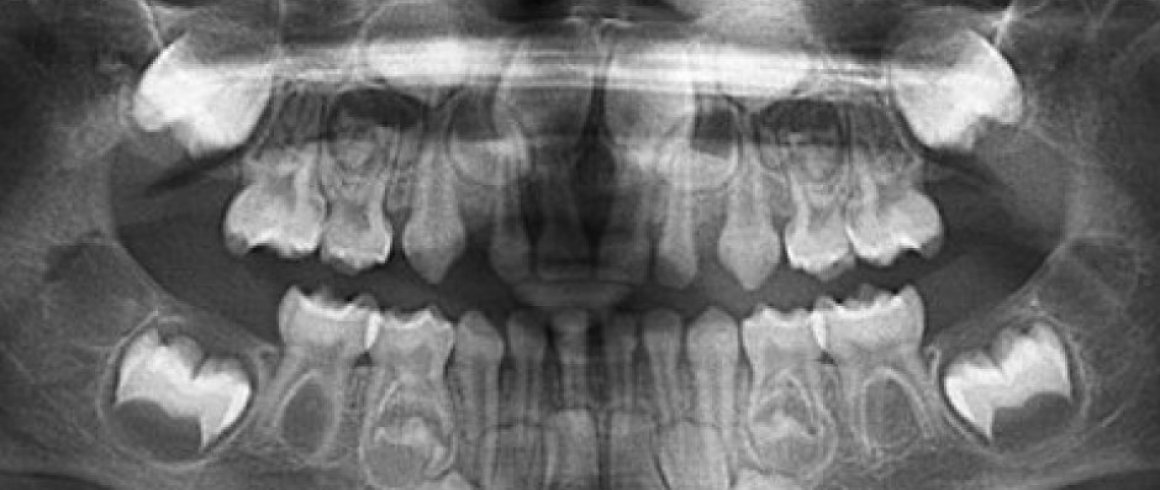

- Panorámica

- Documentación Ortodontica

- Análisis Cefalométrico Lateral

- Análisis Cefalométrico Frontal

- Edad Ósea